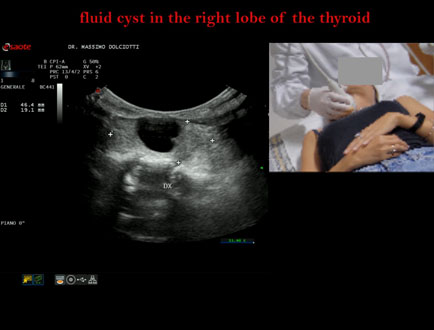

Data inserimento: 05/11/2025

Ecografia del: 27/10/2025

Strumento: Esaote MyLab Eight

Sonda: Lineare Multifrequenza 3-13 MHz e Volumetrica Multifrequenza 1-8 MHz

Età Paziente: F 44 anni

Motivazione dell'esame: rapida comparsa di tumefazione in sede cervicale anteriore, lievemente dolente alla palpazione.

Commento all'esame: le immagini ed il video documentano al terzo medio del lobo destro della tiroide, formazione anecogena, a margini regolari, senza segni di vascolarizzazione, delle dimensioni di 16,9 x 19 mm, da ricondurre a cisti liquida.

Conclusioni: cisti liquida al lobo destro della tiroide (fluid cyst in the right lobe of the thyroid).